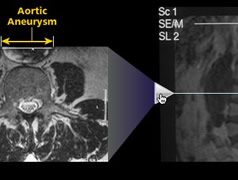

![[Interactive MRI Demo]](/images/paolini_slider.jpg) |

For the Law Offices of Paolini & Haley in Boston, I created a multimedia presentation in late 2007 that formed the centerpiece for a successful medical malpractice case. The software I programmed incorporated videos, interactive images, and hundreds of pages of documents — with special code so highlighted quotes could leap out at the viewer —

all within an easily-navigable interface.

I designed and programmed this interactive MRI demo to show why the diagnosis should have been made based on the MRI images from the case.